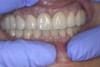

The next stages of prosthetic dental treatments were continued in the regular hospital dental clinic without any relaxants or tranquilizers. However, it is important to note that the patient was regularly using medical cannabis. During the try-in of the bridges (Figure 4) the patient was very cooperative and, most significantly, had almost no involuntary movements.

Fig 4. Front view of restoration showing the asymmetric smile line.

Figure 4